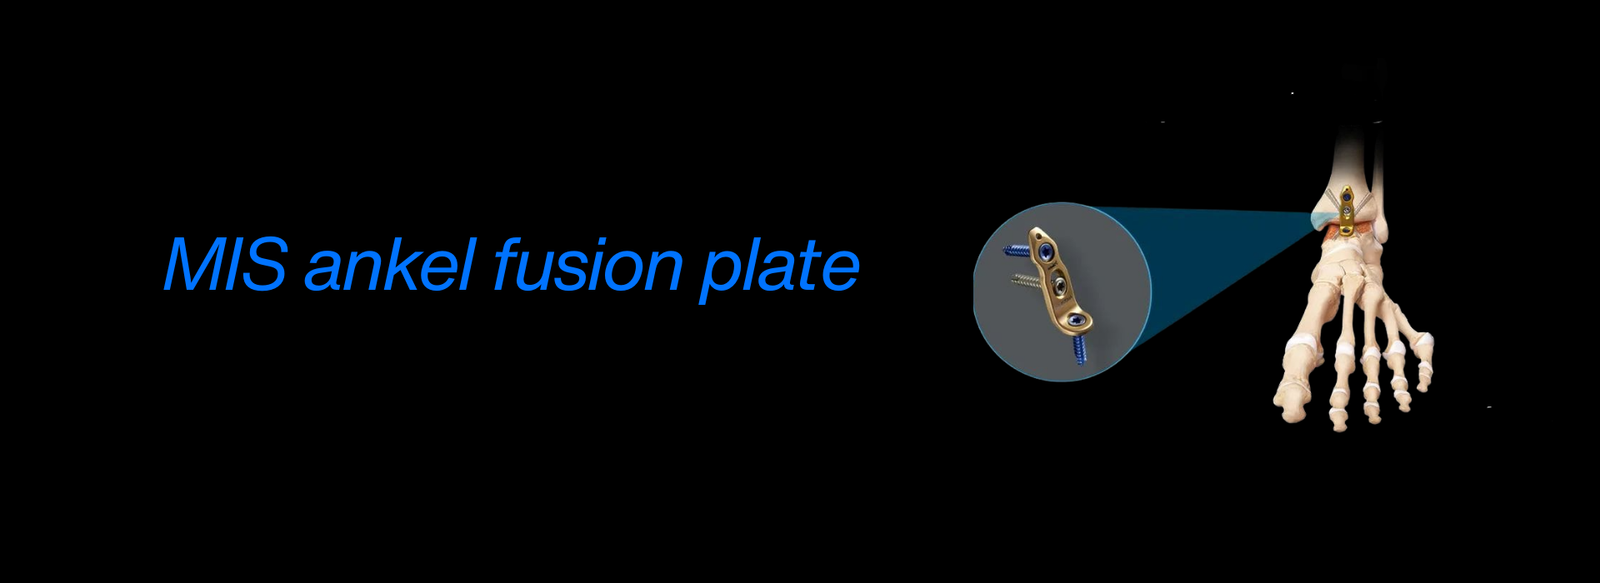

AO Trauma Basic & Advanced: Specialization in trauma surgery related to bone fractures and injuries, learned through the prestigious AO Foundation, an international group focused on trauma care.